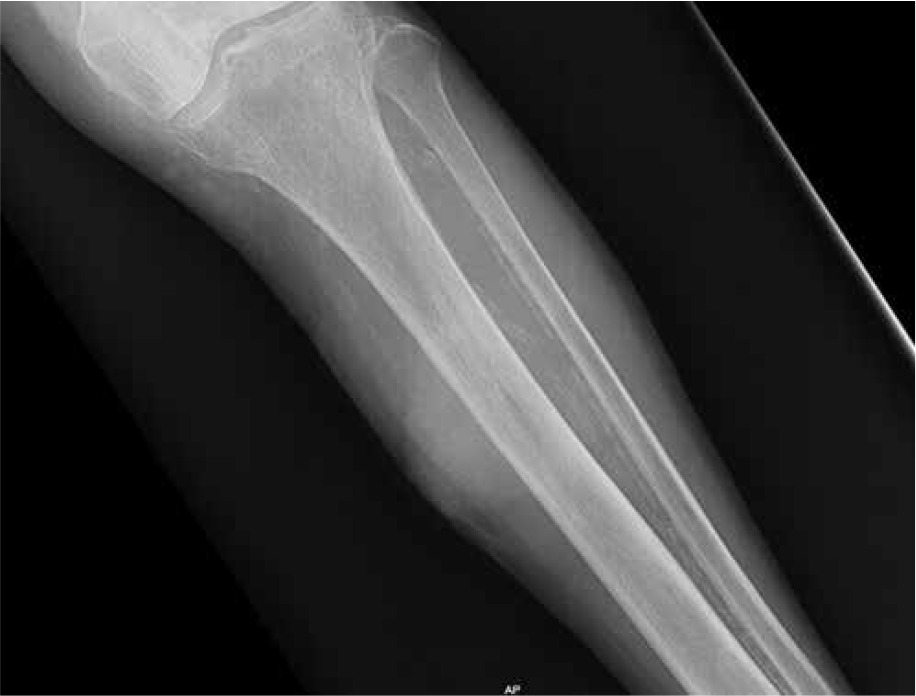

The patient underwent emergency surgery, and osteosynthesis was achieved by means of external bone fixation (Figure 3). Intraoperatively, a biopsy of the altered bone tissue from the fracture site was taken. The pathological examination revealed metastatic colorectal adenocarcinoma. During the hospitalization, a broad diagnostic work-up was undertaken. MSCT of the abdomen, thorax, and lower extremities was obtained and revealed rectal tumour with no signs of metastases apart from the osteolytic lesion in the fractured left tibia (Figures 4 A–C). Furthermore, a colonoscopy was done, and a circular mass in the upper rectum, about 12 cm from the anal verge, was found (Figure 5). Pathological examination of the tumour specimen obtained at colonoscopy confirmed a moderately differentiated primary adenocarcinoma of the rectum. The patient was presented at a multidisciplinary tumour-board, where it was decided to perform a resection of the primary tumour and a femoral amputation prior to chemotherapy.

Figure 4

A – Coronal plane of MSCT – osteolytic tibial lesion, B – Axial plane of MSCT – osteolytic lesion in the diaphysis of the left tibia covering almost all the diameter of the bone in this site, C – Axial plane of abdominal MSCT showing rectal mass